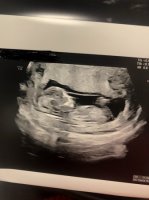

Fikk en skikkelig fin opplevelse på tul i dag. Det var magisk å se lille sprelle inni der. Helt utrolig! Fingre og tær viste også <3 9+5, satt tilbake en dag.

Så hærligJubler for perfekt ultralyd idag! Flott neseben og nakkefold, og med all sannsynlighet er det ei lita jente som spreller inni der!

14+1 etter menstermin, hun satte meg til 13+6 etter ul. Sa det var lurt at vi hadde venta såpass lenge (tok en på 8+5 og da), for nå var det mye lettere å finne «alt». Det blir mye mer moro, som hun sa. Gøy å se lillemor sprette og sprelle rundt inni der!Så hærligHvor langt på vei?